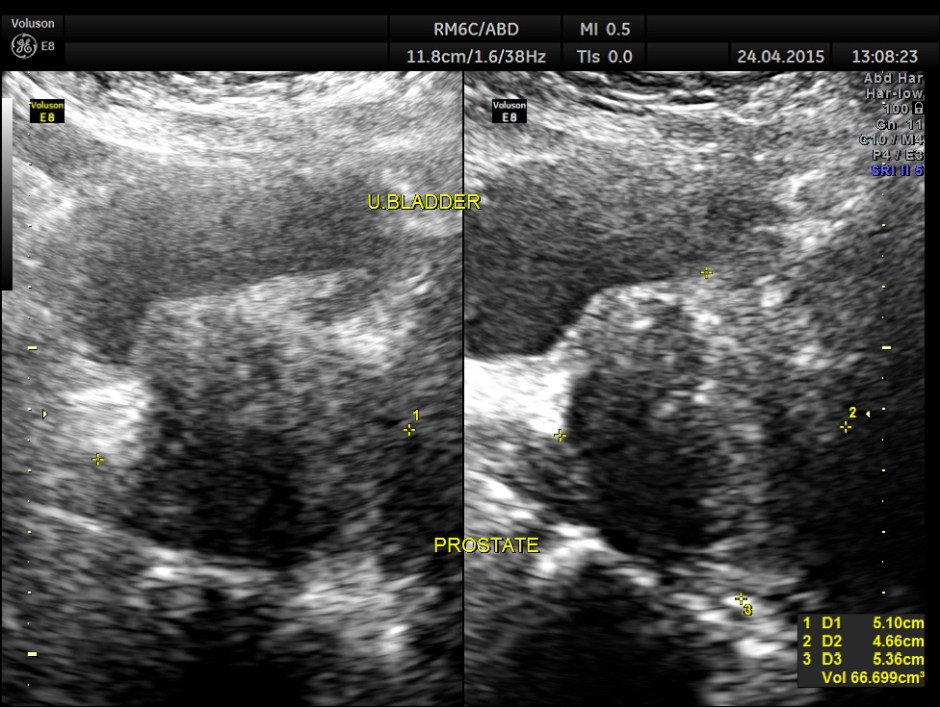

His ultrasound at present showed :

Prostate shows moderate hypertrophy with a volume of 66.6 cc.